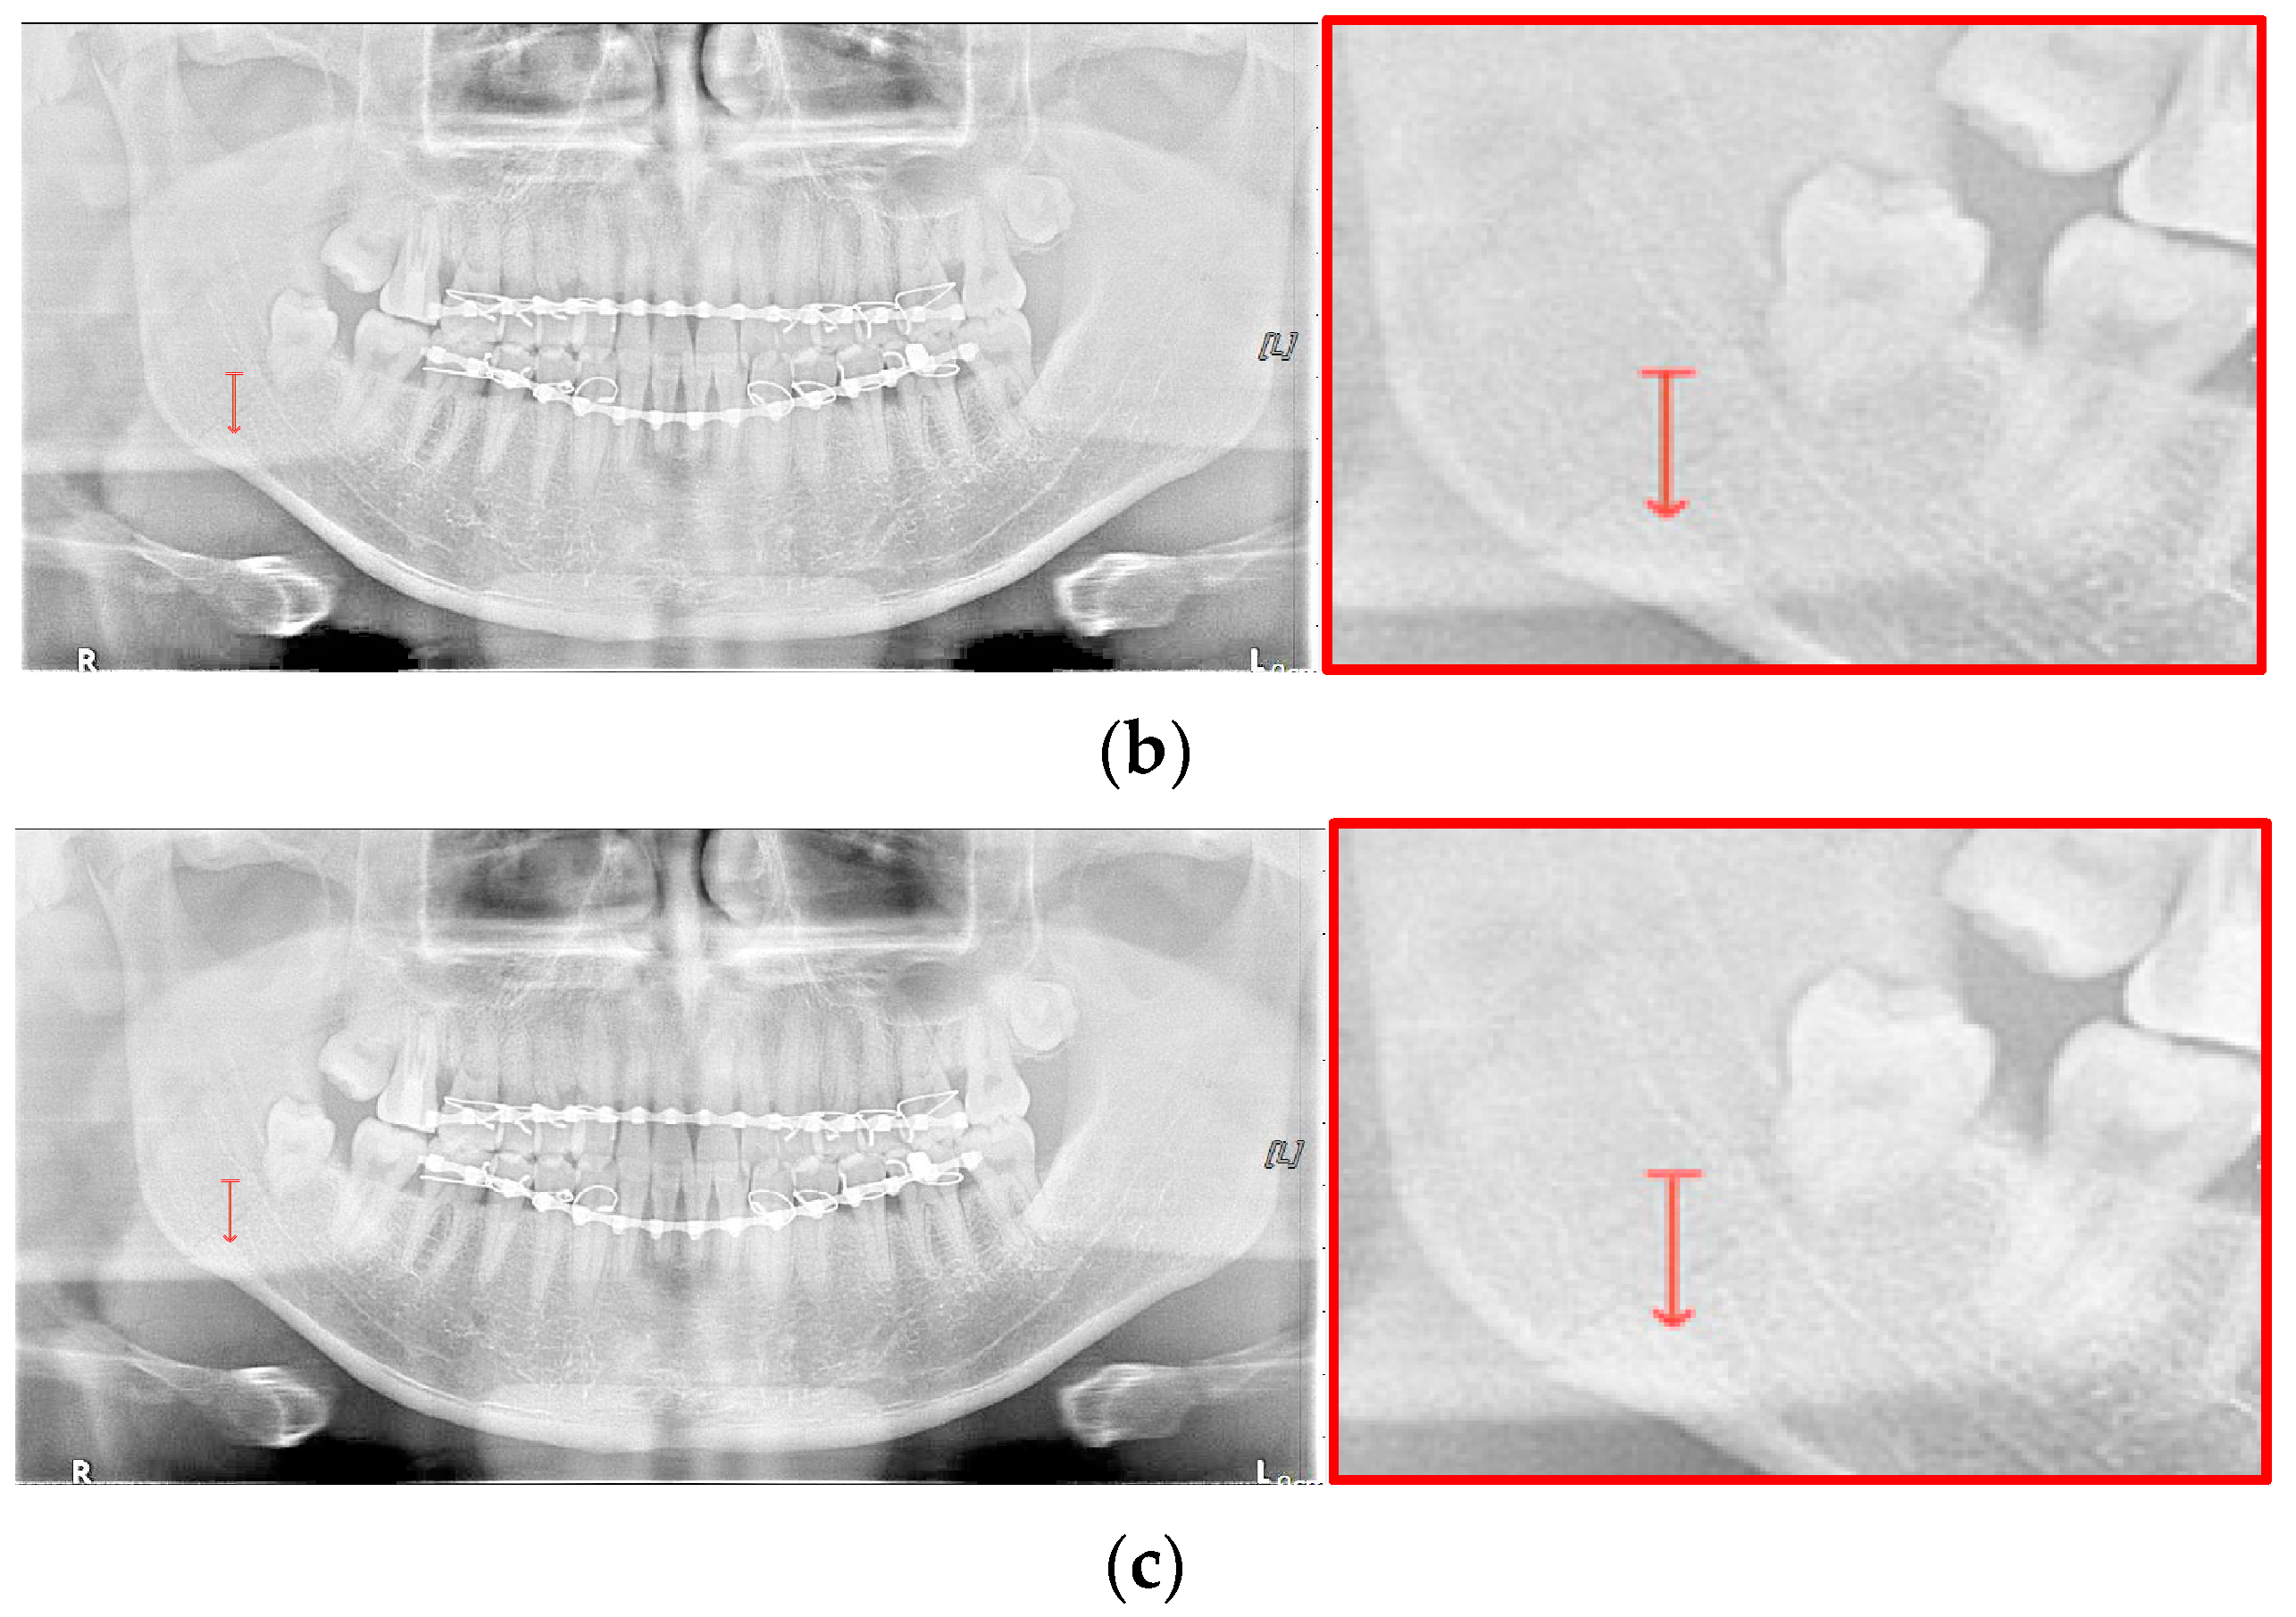

For the case of Figure 12 images, it is possible to check the amount of local contrast improvement from the line profile information. In order to compare the changes in pixel brightness near angle fracture in the normal, SLAT and MLAT panoramic radiographs, the result of line profiles are shown in Figure 14 and Table 7. When comparing the maximum pixel brightness, minimum pixel brightness, average pixel brightness, and standard deviation in the line profile of the straight arrow near the angle fracture site, the normal panoramic radiograph has the largest standard deviation value of 5.6. Due to the characteristics of LAT processing, a dark area increases contrast, but as it becomes a bright area, contrast is maintained or slightly lowered.

Figure 14.

The comparison of SLAT and MLAT processing with line profiler: (a) normal radiograph, (b) SLAT-processed, and (c) MLAT-processed.

However, except for some bright radiograph images, the effect of LAT processing is evident in most dark radiograph images. As shown in Figure 15, most of the LAT-processed radiographs have a high standard deviation value compared to the normal radiographs. In Table 7, the LAT-processed panoramic radiographs shows the higher deviation values of 14.6 and 15.2, which are reasonably more than 9.3 of the normal panoramic radiograph.

Figure 15.

The comparison of SLAT and MLAT processing with line profiler: (a) normal radiograph, (b) SLAT processed, and (c) MLAT processed.